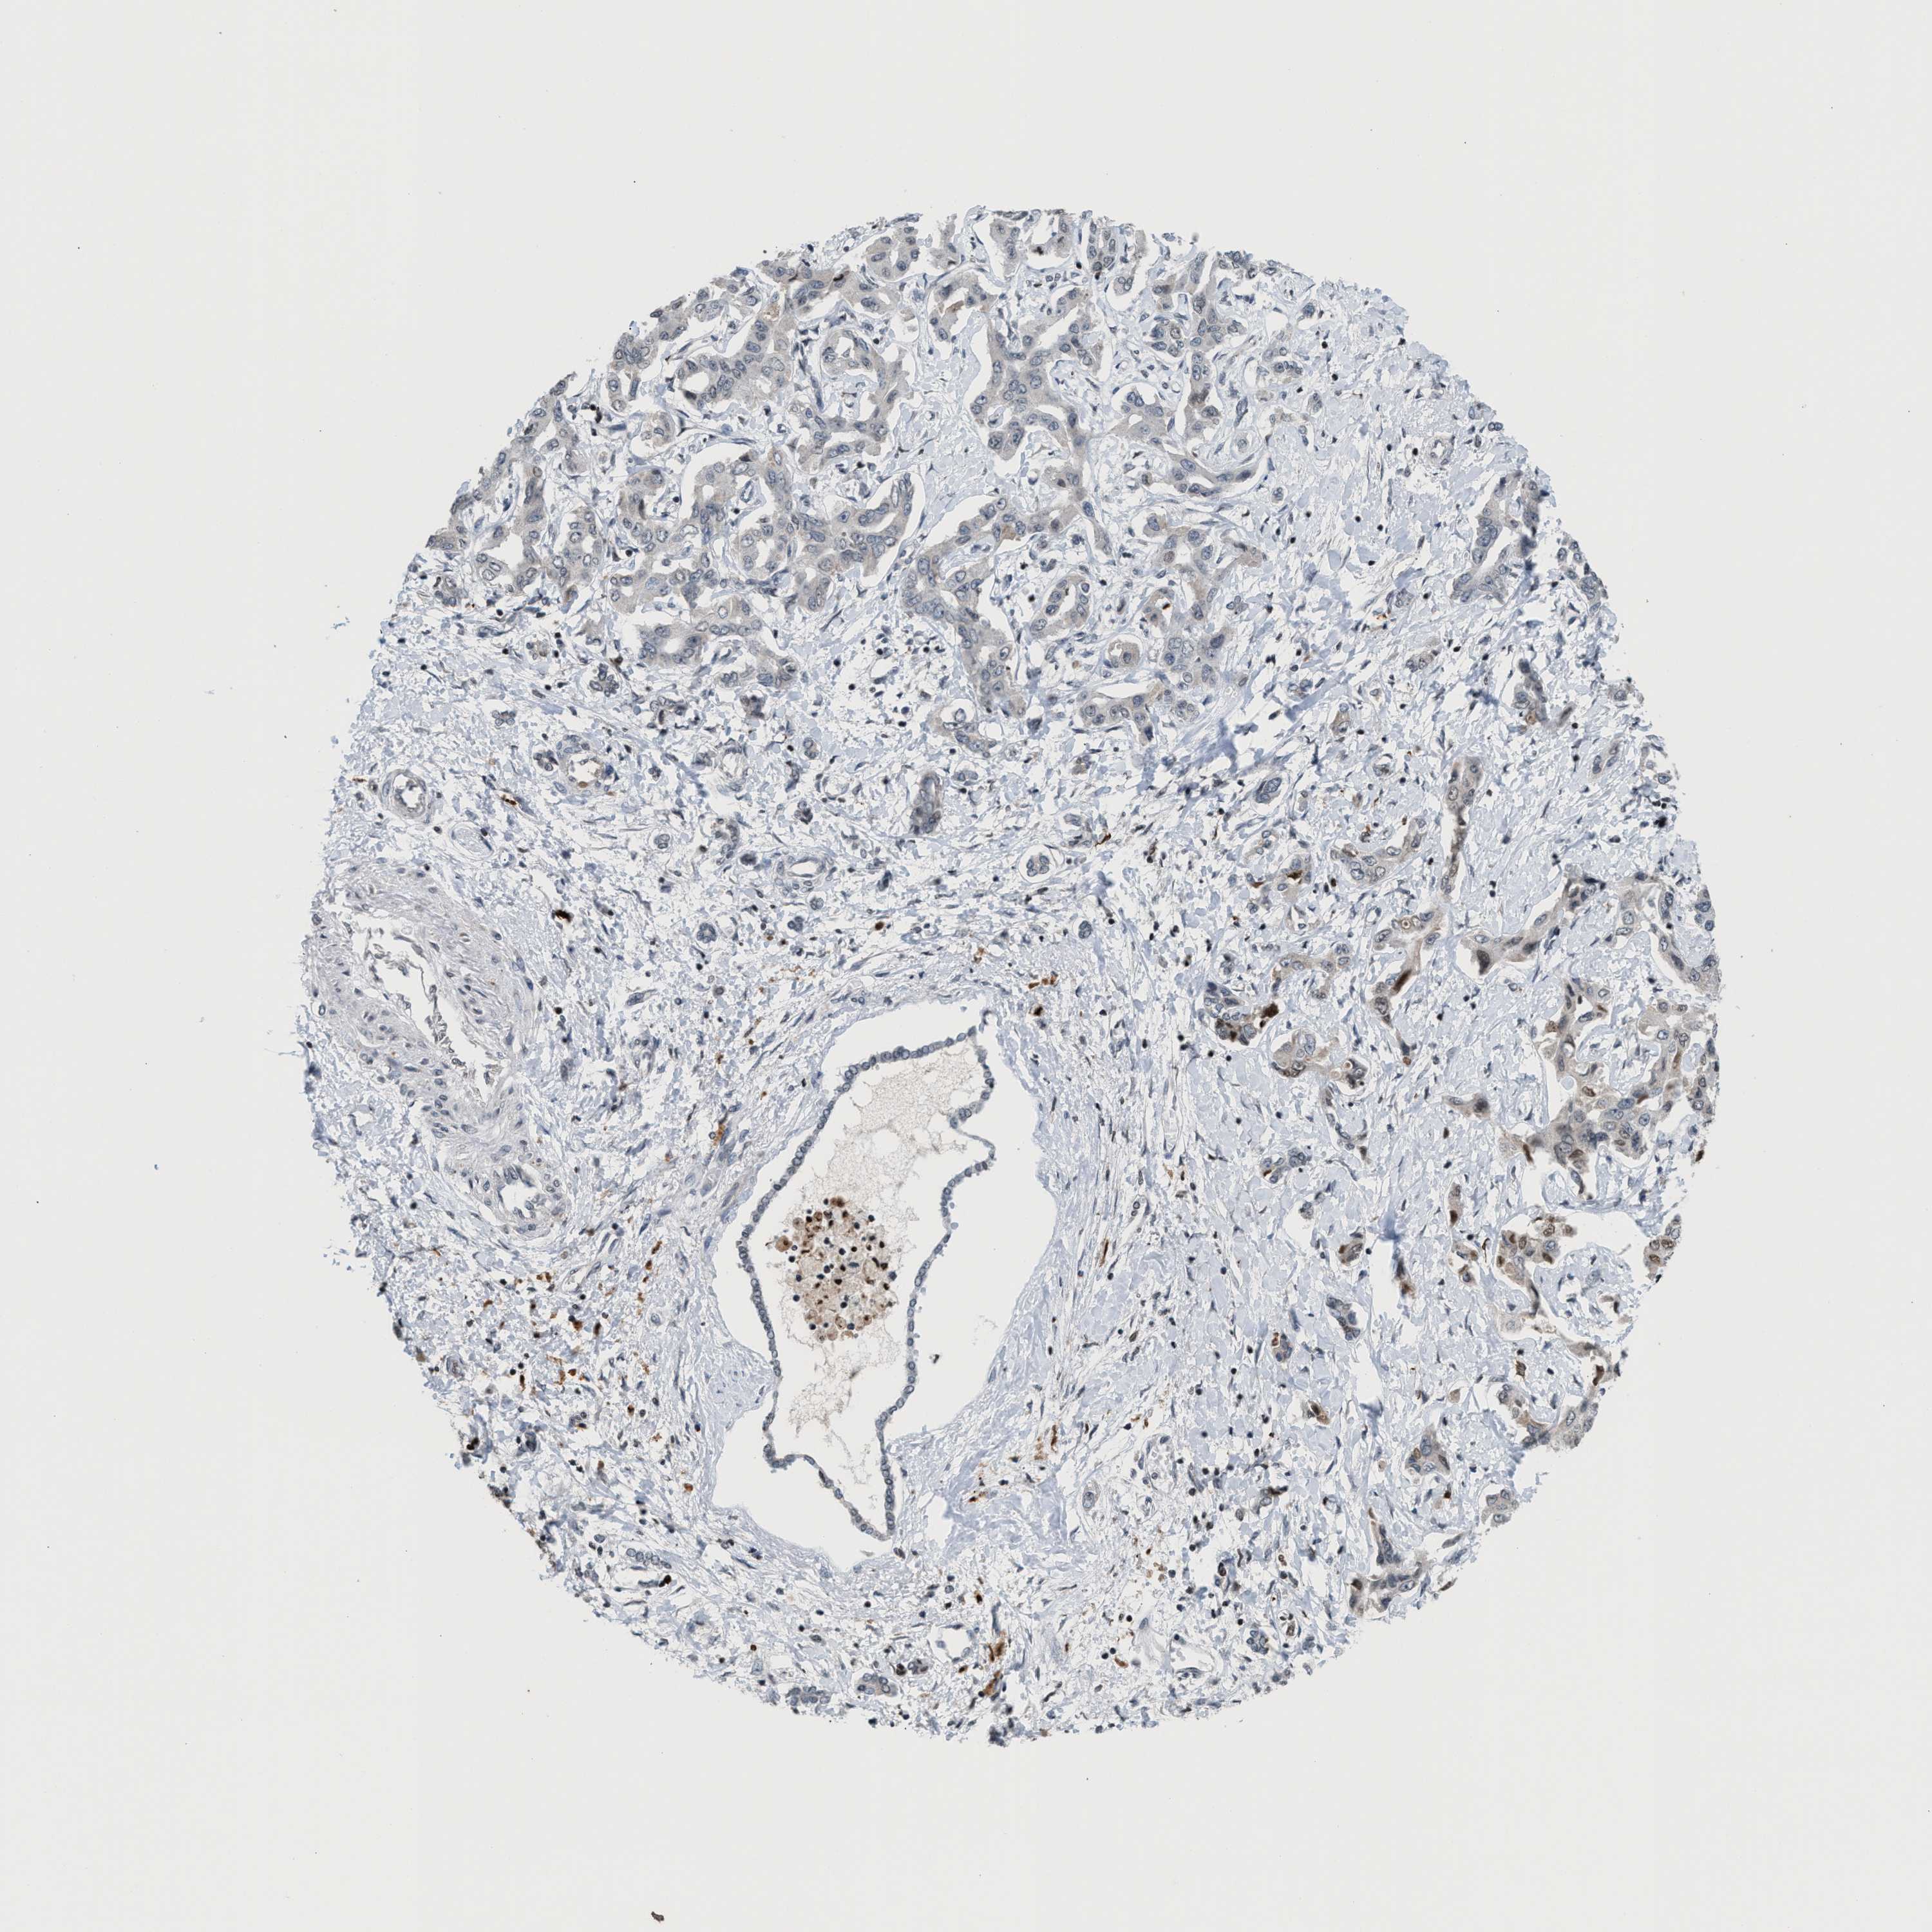

LIVER CANCER - Protein expressioni

A mouse-over function shows sample information and annotation data. Click on an image to view it in a full screen mode. Samples can be filtered based on level of antibody staining by selecting one or several of the following categories: high, medium, low and not detected. The assay and annotation is described here.

Note that samples used for immunohistochemistry by the Human Protein Atlas do not correspond to samples in the TCGA dataset.

Antibody stainingi

Antibody staining in the annotated cell types in the current human tissue is reported as not detected, low, medium, or high, based on conventional immunohistochemistry profiling in selected tissues. This score is based on the combination of the staining intensity and fraction of stained cells.

Each image is clickable and will lead to virtual microscopy that enables deeper exploration of all samples and also displays staining intensity scores, fraction scores and subcellular localization as well as patient and tissue information for each sample.

Antibody HPA022470

Antibody HPA031079

Staining

High

Medium

Low

Not detected

Intensity

Strong

Moderate

Weak

Negative

Quantity

>75%

75%-25%

<25%

None

Location

Nuclear

Cytoplasmic/membranous

Cytoplasmic/membranous,nuclear

Cholangiocarcinoma

Carcinoma, Hepatocellular, NOS